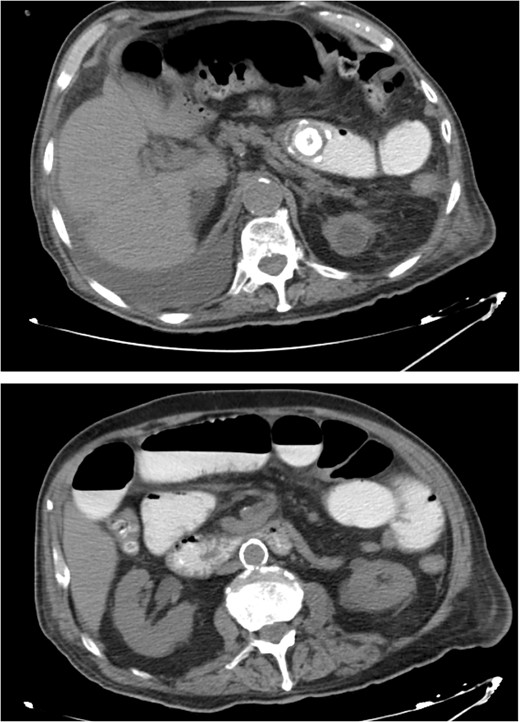

An 80-year-old male presented to the emergency department complaining of intermittent abdominal pain, vomiting and intense nausea beginning 3 days prior. The patient reported a medical history of type 2 diabetes mellitus, hypertension and coronary artery disease. Upon arrival, he was afebrile (T: 37°C) and tachypneic (24 breaths/minute), the following vital signs were: heart rate 98 bpm, blood pressure 160/95 mmHg, oxygen saturation 96%. Examination of the abdomen revealed significant hypoactive bowel sounds and diffuse tenderness. Laboratory investigations revealed a white blood cell count of 8.190/mm3, hemoglobin of 15.9 g/dl, and elevated levels of C - reactive protein of 15.94 mg/dl (N < 0.5 mg/dl) whereas the rest of the laboratory parameters were within normal limits. The patient initially underwent plain chest and abdomen radiographs which revealed small bowel gas-fluid levels indicating intestinal obstruction and intravenous fluids resuscitation was initiated. A CT scan with IV and oral contrast which was later performed revealed gastric, duodenal and small bowel loops distension and swelling caused by a high attenuation mass within the intestinal lumen at the jejunum-ileum transition which was attributed to a gallstone. Α second possible gallstone of smaller diameter was located in jejunum loops, and a cholecysto-duodenal fistula, of air and oral contrast in the gallbladder, pneumobilia, and intraperitoneal fluid in Douglas’s pouch were also present (Fig. 3).

CT images with oral and IV contrast revealed presence of air and oral contrast in the gallbladder and small bowel obstruction caused by a mass in the jejunum–ileum transition attributed to a gallstone.